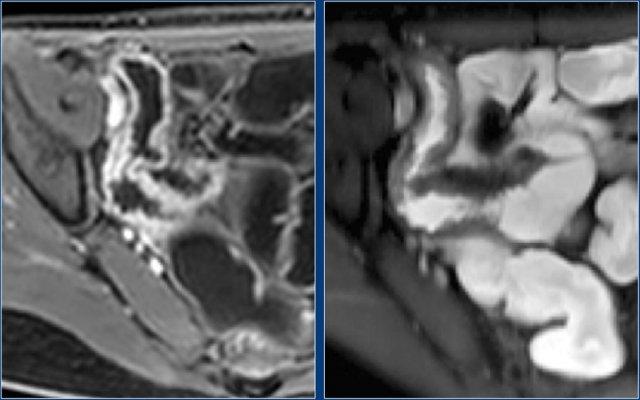

Hình ảnh T1W sau tiêm thuốc tương phản mặt phẳng coronal cho thấy hẹp tại vùng nối hồi manh tràng (trái). Không thấy giãn ruột trước chỗ hẹp rõ ràng. Chỗ hẹp không thể vượt qua được khi nội soi (phải).